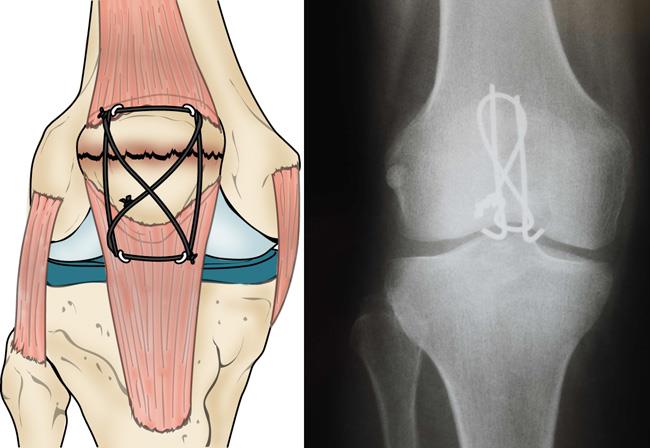

Fracture after Knee Replacement Surgery Complete Orthopedics store, Peri prosthetic trans patellar fractures after Total knee store, Post op Knee Pain Common causes store, Peri prosthetic trans patellar fractures after Total knee store, Patella Fracture Baton Rouge Kneecap Fracture Knee Joint Pain store, Patellar Fractures Broken Kneecap OrthoInfo AAOS store, Patellar Fractures Broken Kneecap OrthoInfo AAOS store, Treating Patella Fracture Broken Knee Cap in Plano Frisco store, Patella Fracture Orthopaedic Trauma Association OTA store, Patellar Fractures Broken Kneecap OrthoInfo AAOS store, Patella Fracture treatment Patella Fracture surgery store, Clunking Knee after Knee Replacement Complete Orthopedics store, Kneecap Fractures Patella Fractures Johns Hopkins Medicine store, Knee Replacement Surgery Details Recovery store, My knee still hurts after knee replacement surgery is this normal store, Pain after Knee Replacement Complete Orthopedics Multiple NY store, Patellar Fractures Broken Kneecap OrthoInfo AAOS store, Patellar Fracture Fractured Knee Cap PhysioAdvisor store, Patellar Kneecap Fracture Boston Medical Center store, Patella Fracture Orthopaedic Trauma Association OTA store, Patella Fracture Broken Knee Cap orthopedic specialist prescott store, Swelling after Total Knee Replacement Complete Orthopedics store, What is a Partial Knee Replacement store, Knee Replacement Complications Problems After Knee Surgery store, Patellar Kneecap Fracture Boston Medical Center store, Patella Fracture or a Broken Kneecap store, Patellar Fractures Broken Kneecap OrthoInfo AAOS store, Patella Fracture Broken Knee Cap Orthoriverside store, Benefits of Chiropractic Therapy After a Knee Replacement store, Complex Total Knee Replacement Boston MA Knee Fracture Worcester MA store, After Surgical Kneecap Alignment Patient Education UCSF Health store, Patella Fracture Repair store, Knee Replacement Surgery Risks and What to Expect store, Patella Fracture Orthopaedic Trauma Association OTA store, KNEE REPLACEMENT SURGERY AND SSD BENEFITS store.